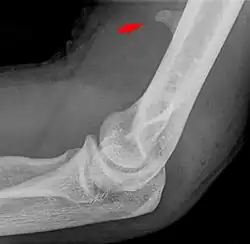

Der Processus supracondylaris ist eine seltene atavistische Bildung an der vorderen ulnaren Seite des distalen Endes des Oberarmknochens (Humerus), etwa 6 bis 7 cm proximal des Gelenkspaltes. Synonyme sind Processus supracondylicus, Tuberculum supratrochleare, Humerussporn und englisch Humeral supracondylar spur. Es handelt sich um einen knöchernen Fortsatz, der bei 0,7 % – 2 % aller Menschen vorkommt.[1] Die Erstbeschreibung geht auf den Anatomen F. Tiedemann im Jahre 1822 zurück.[2] (zitiert nach[3])

Die Arteria brachialis und der Nervus medianus verlaufen bei vorhandenem Processus supracondylaris durch einen osteofibrösen Kanal, den Canalis supracondylicus, der zur Kompression der beiden Strukturen führen kann.[4]